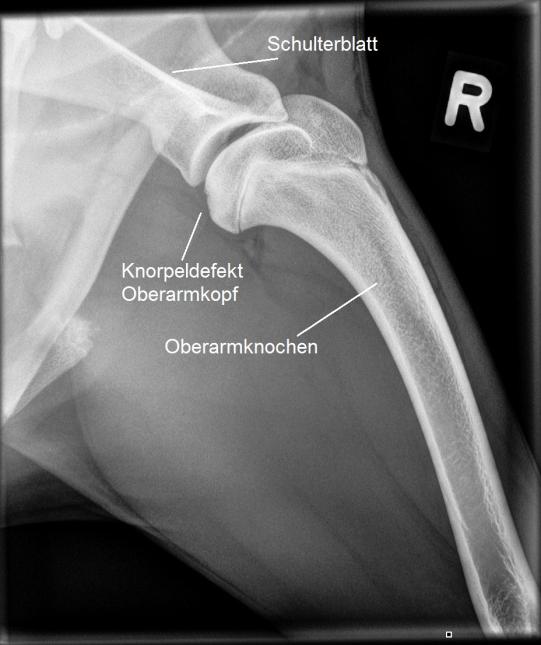

Die Ellbögen erscheinen verhältnismässig unauffällig, allerdings sind fragliche Veränderungen an einem kleinen Gelenksfortsatz (Processus Coronoideus) nicht ganz ausgeschlossen. In den Schultergelenken werden wir jedoch eindeutig fündig: Beide Gelenke zeigen im Bereich des Oberarmkopfes eine Schädigung des Gelenkknorpels an der typischen Stelle im hinteren Teil des Gelenkes: Inox leidet an einer sogenannten Schulter-OCD (Osteochondrosis Dissecans).

Bei diesem wachsenden Sporthund ist es wichtig, dass das Problem baldestmöglich aggressiv angegangen wird. Inox wird an die Orthopädieabteilung des Tierspitals Bern überwiesen, wo mittels Gelenksspiegelung die Diagnose bestätigt und das Problem operativ angegangen wird: Mit den ins Gelenk vorgeführten Instrumenten werden die losen Knorpelteile entfernt und der unterliegende, freiliegende Knochen debridiert (d.h. von losem Gewebe befreit). In der Folge wird der Knorpeldefekt im Zuge der Heilung durch Faserknorpel ersetzt.